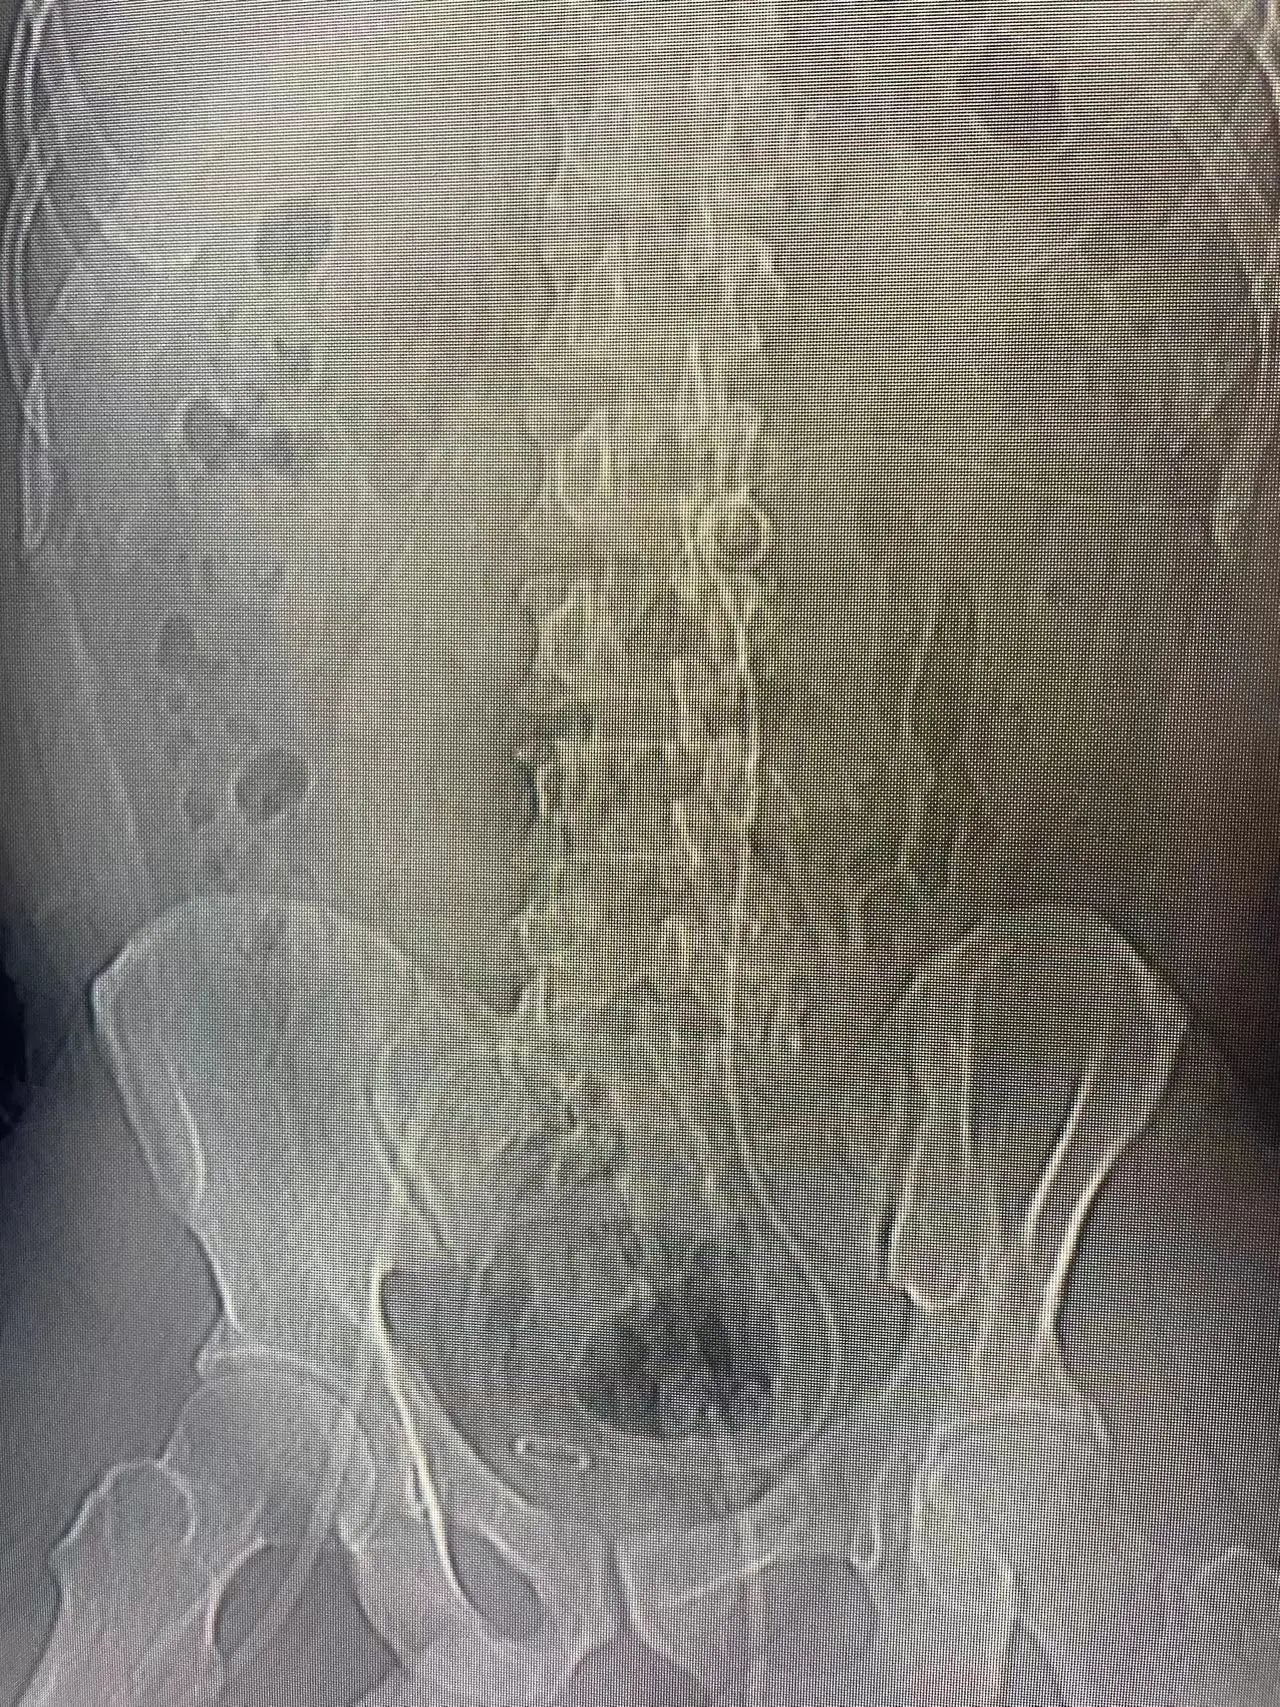

今年47岁的张某两年前开始出现间歇性腰痛,医院诊断为左侧输尿管结石,但并未引起重视。半个月前,张某左侧腰背部突发剧烈疼痛,为求进一步治疗,来到我院普外科就诊。经普外科洪崟淏医生结合辅助检查诊断为“左侧输尿管多发结石、肾脏多发结石并左肾积液”,左侧输尿管上段结石较大(3.5cm)并且阻塞输尿管,造成左肾积水,左肾周还有少许的渗出。如果不及时处理可能会导致左侧肾功能衰竭,或者感染加重,诱发脓毒血症危及生命。

患者除结石直径较大外,位置还处于第四腰椎处,属于难治性输尿管结石,一旦打孔偏斜,术中操作时很容易造成肾脏撕裂,且患者输尿管腔内严重狭窄,多项难题叠加,增加了手术的复杂性,更增加了手术难度。